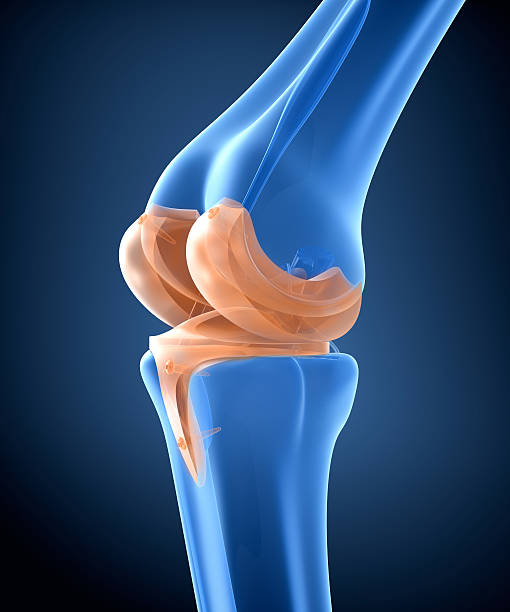

무릎연골은 무릎뼈에 가해지는 충격을 흡수하는 완충장치로 쓰면 쓸수록 닳을 수밖에 없습니다. 이러한 연골은 뼈와 유사한 성분이지만 뼈와 달리 칼슘을 함유하지 않아 뼈처럼 딱딱하지만은 않으며 탄력이 강하고 고무와 유사합니다. 이처럼 연골은 다쳐도 아프지 않기 때문에 치료를 늦추게 되고 병을 키우는 결과가 나올 수 있습니다. 하지만 연골 손상이 더 걱정되는 이유는 연골은 혈관이 없어 한번 손상되면 스스로 치유되거나 재생되지 않는다는 점입니다. 심한 경우에는 손상된 연골이 치유되지 않고 계속 퇴행하며 결국 퇴행성 관절염으로 진행됩니다.

무릎연골은 대퇴골과 경골을 각각 3~4mm 두께로 감싸 관절에 가해지는 충격을 흡수하여 관절이 원활하게 움직일 수 있도록 하기 때문에 심한 충격이나 잘못된 자세로 계속 자극하면 연골이 닳거나 부러질 수 있어 일상 생활에서 관리가 필요할 수 있지만 연골에는 신경이 없어 찢어지거나 닳아도 아프지 않아 연골이 마모되더라도 연골이 아픈 것이 아니라 아래의 뼈가 노출되어 통증을 유발하기 때문에 연골이 손상되었다면 스스로 치유되거나 재생되지 않는다는 점이기 때문에 미리미리 원인을 알고 대비해야합니다.